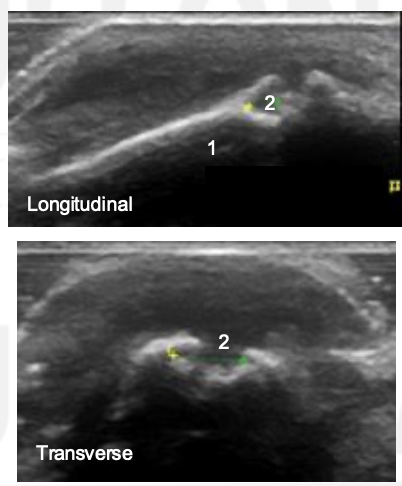

What view is this?

PIP

Synovium

Extensor Tendon

Proximal Phalanx

Middle Phalanx